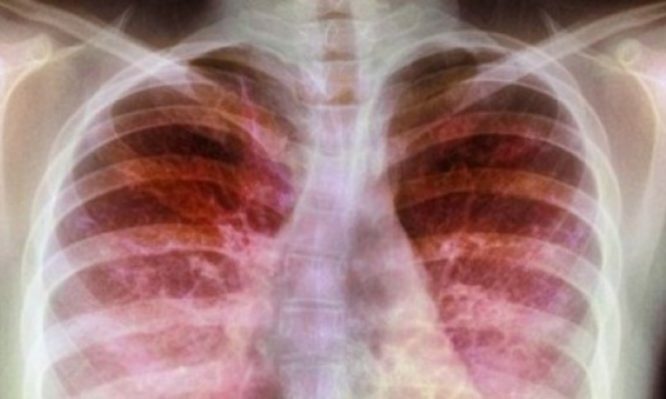

Το τεστ ιδρώτα αποτελεί την πλέον αναγνωρισμένη μέθοδο διεθνώς για την ανίχνευση μικρών ασθενών που πάσχουν από κυστική ίνωση. Το ΙΑΣΩ Παίδων, θέλοντας να παρέχει ό,τι καλύτερο στη φροντίδα των παιδιών, αναβαθμίζει τις υπηρεσίες του και επενδύει σε ιατρικό εξοπλισμό τεχνολογίας αιχμής.

Το 4-5% του γενικού πληθυσμού, δηλαδή 1 στα 20 έως 25 άτομα θεωρείται ότι είναι φορέας του παθολογικού γονιδίου (περίπου 500.000 Έλληνες είναι φορείς). Ως εκ τούτου, υπάρχει αυξημένη πιθανότητα να γεννηθεί παιδί με κυστική ίνωση. Τα συμπτώματα που παρουσιάζει συνήθως κάποιος που νοσεί είναι κυρίως χρόνιος βήχας, βρογχίτιδες ή υποτροπιάζουσες βρογχίτιδες, ανεπαρκής πρόληψη βάρους.